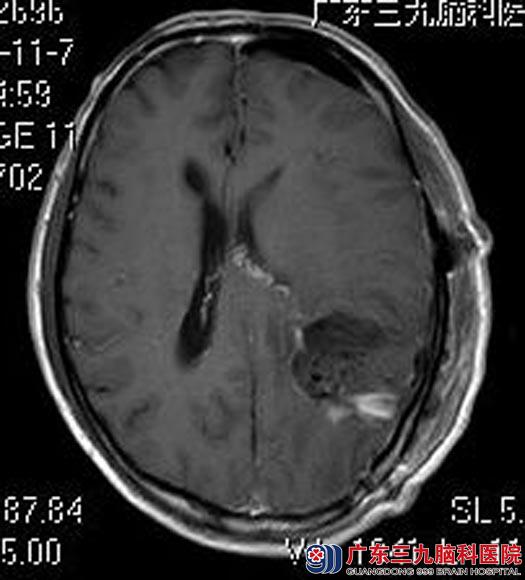

为进一步了解病情,林先生来到广东三九脑科医院,MR检查提示:左侧颞顶叶示类圆形病灶,大小约5.3cm×4.0cm×5.5cm,可疑肿瘤卒中。

综合神经外科鲁明主任主刀,在全麻唤醒麻醉下行左侧颞顶叶肿瘤切除术。术中唤醒,彩超再次定位肿瘤位置,显微镜下见肿瘤呈囊性结构,质软,灰黄色胶样,血供一般,镜下全切病灶。术中患者语言、肢体活动功能正常,手术顺利结束。无术后并发症出现,康复出院。